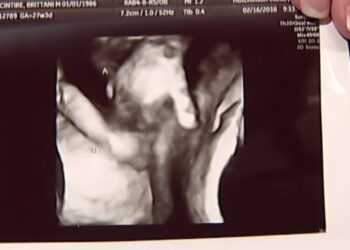

Συγκλονιστικό! Έμβρυο αποχαιρετάει το δίδυμο αδελφάκι του που πεθαίνει(Video)

Μέλλουσα μητέρα στο Κάνσας ήρθε αντιμέτωπή με μια δυσάρεστη είδηση που αφορά την εγκυμοσύνη της και την οποία έμαθε από ...